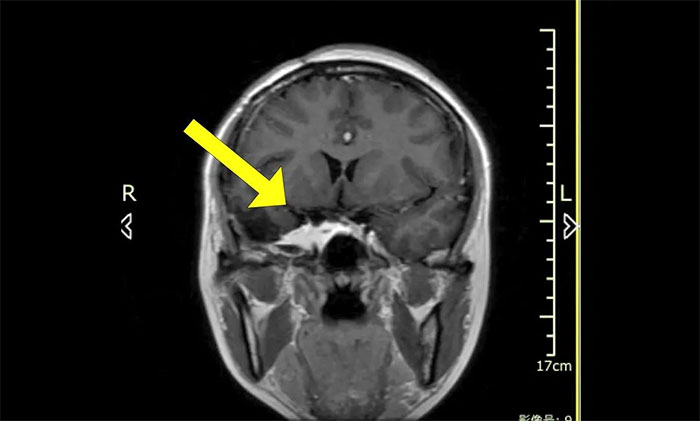

陈琦主任团队根据患者病情,精心设计了分期治疗的靶区和治疗剂量,用伽玛射线聚焦于病灶,使病变组织凋亡并逐渐阻断血供,从而达到治疗目的。完成治疗后患者顺利出院,半年后来院复查,病灶较前明显缩小。

▲ 治疗后病灶明显缩小